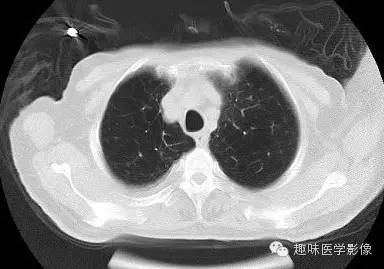

【病例】肺脓肿1例CT影像特点

男,71岁,发热待查。

[影像描述]

双肺多发无壁低密度区,以右肺下叶底部为主。右肺下叶见大片不规则实变阴影伴多发空洞影,实变肺组织内见支气管气象,右肺下叶支气管局部显示不清。纵隔内见淋巴结。右侧胸腔内见积液影,邻近胸膜肥厚。主动脉、冠状动脉钙化。

右肺下叶肺脓肿、肺炎伴胸腔积液,肺气肿、肺大泡。